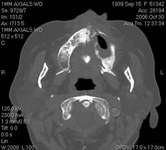

The patient also had extensive bone loss in her anterior mandible (Figure 11).To avoid performing extractions, a simple composite splint was placed between the partial dentures (Figure 12 and Figure 13). The splint reduced the mobility of the teeth and made them less likely to be knocked out during any surgical intubation procedure. As stated earlier, spontaneous osteonecrosis is also possible. Figure 14 shows a had noticed the foreign material, but chose not to act on it. When the material was removed in the dental office (Figure 15 and Figure 16), blood streamed from the nose, so severely that the patient had to be sent to an ear, nose, and throat (ENT) physician. The ENT took a computed tomography scan, which showed a large radiolucency in the upper left quadrant where the foreign material once had been (Figure 17). A review of the radiograph (Figure 18) showed that bone in the maxillary arch had decreased mineral density compared with the mandible. The biopsy report found necrotic bone with organisms consistent with actinomyces. These findings were consistent with biopsies found in the literature.22 When the patient returned for a 1-week follow-up, she still had signs of infection and the site had a foul odor and a discharge (Figure 19). The patient was informed that she should follow up with the ENT and return to the dental office after the infection had been resolved.

Figure 16 Necrotic bone. Figure 17 CT scan showing extensive bone loss. Figure 18 Panoramic radiograph showing decreased bone density.